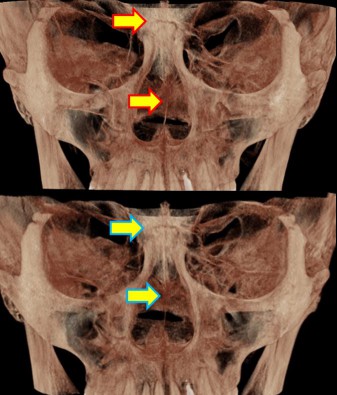

Not long ago, a practicing physician from Prague visited my clinic during orthodontic bracket treatment. She was diagnosed with facial asymmetry and body misalignment, and experienced MCB splint therapy. She was aware that bodily misalignment is related to asymmetry in the facial bones.